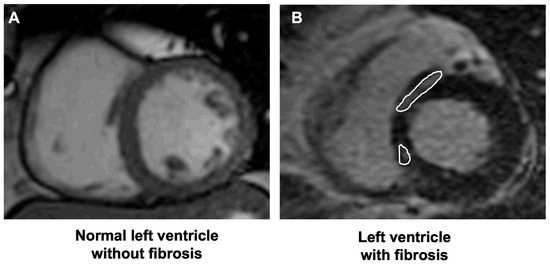

2.2. Cardiovascular Magnetic Resonance